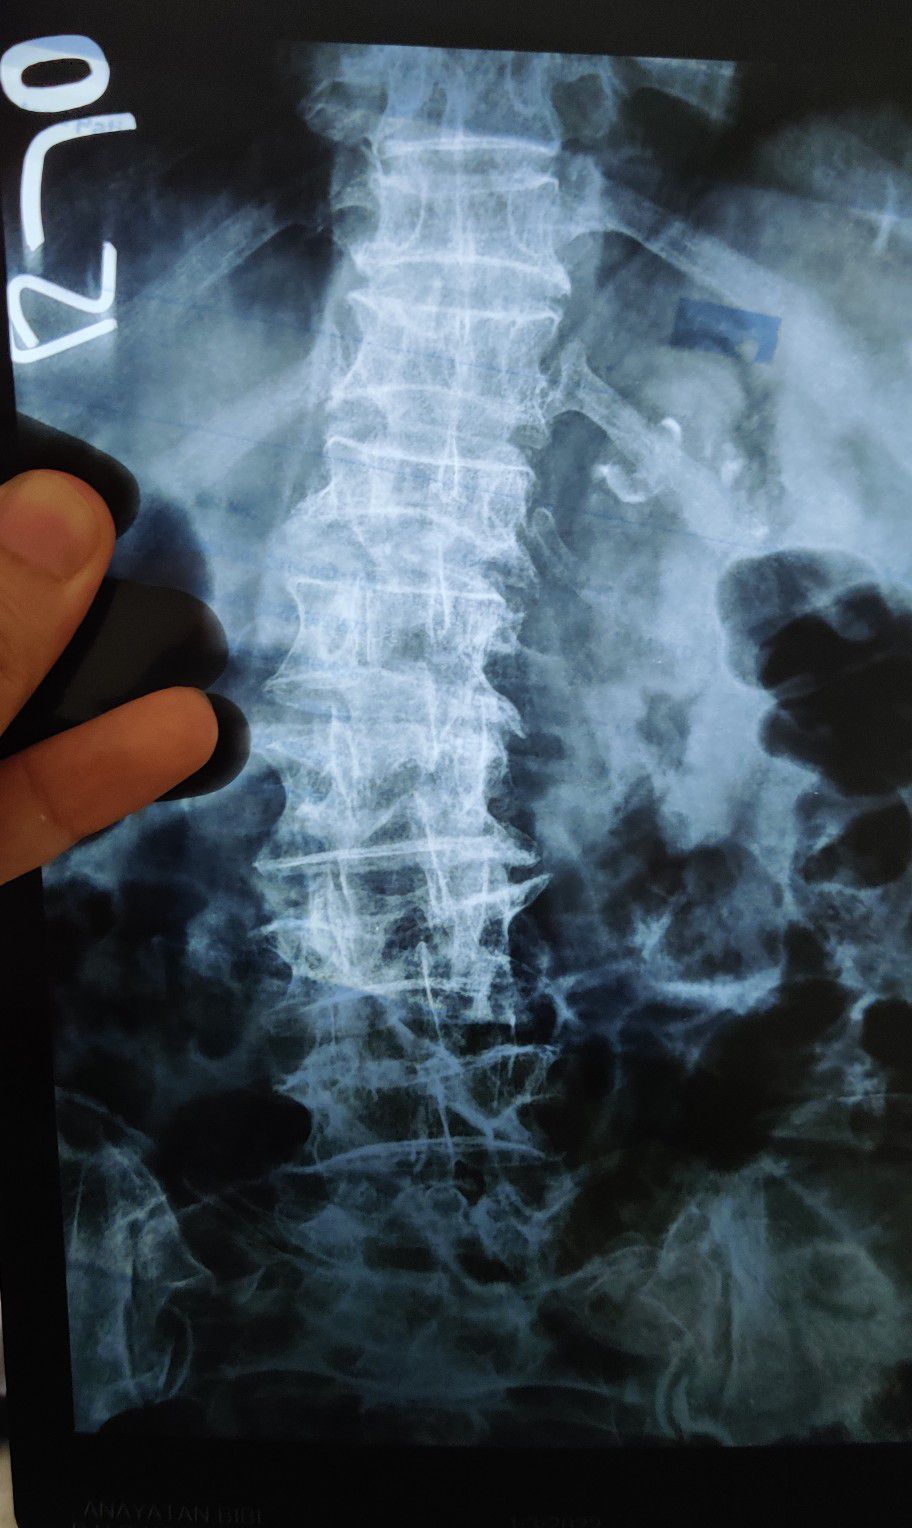

Osteoporosis + Scoliosis

Scoliosis

Osteoporosis